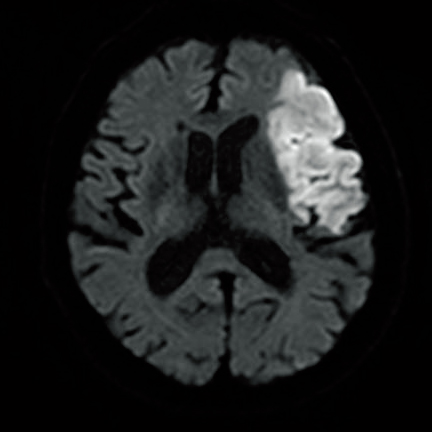

MRIを撮る理由は?

●MRIにより、詳細な原因検索を行うため

次に原因検索のために、必要に応じてMRI(磁気共鳴画像)などが行われます。

MRIでは検査前に、「体内外の金属や貼付薬の確認」「適切な衣類の確認」「身長や体重の把握」などの確認事項が多くあります。またMRIは、CTに比べ時間(20~40分ほど)や費用的な負担もかかりますが、さまざまな撮影条件から詳細な疾患の特定につなげていくことができます。

さらにMRIでは撮影に造影剤(ガドリニウム造影剤)を用いることで、悪性や良性の脳腫瘍の判断や脳膿瘍などの詳細な評価が可能になります(ただし、CTでもヨード造影剤を用いれば脳血管病変などの評価が行えるため、検査の目的によっては「造影CT」を行うこともあります)。

なお造影剤は、腎機能障害、喘息の既往のある患者、造影剤に対するアレルギーがある場合には注意が必要です。特に造影CTの場合、ビグアナイド系の糖尿病薬を内服している患者さんでは、造影剤との併用で乳酸アシドーシスを起こすことがあるため注意が必要です。

いずれにしても、抽出したい画像によってMRIかCTか、また造影剤使用の有無を判断します。